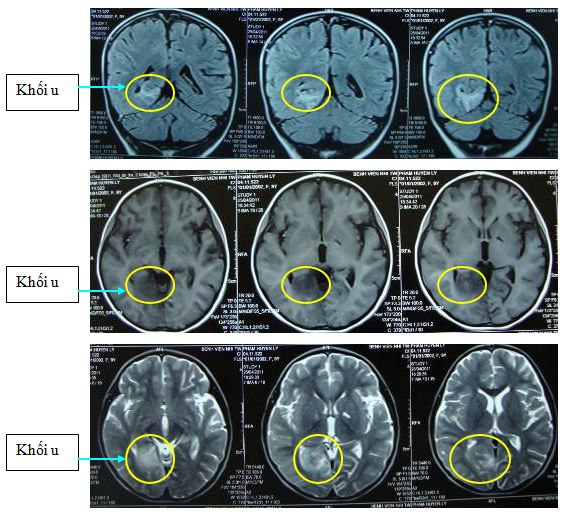

Tại đây bệnh nhân được chụp phim cộng hưởng từ sọ não cho thấy có khối u vùng chẩm phải đường kính 30x30x29mm nghĩ nhiều đến U sao bào (Astrocytoma)

Bệnh nhân được hội chẩn tại Hội đồng hội chẩn ung bướu - Trung Tâm y học hạt nhân và Ung bướu, bệnh viện Bạch Mai với các giáo sư, bác sỹ chuyên ngành ung bướu, y học hạt nhân, nội khoa thần kinh, chẩn đoán hình ảnh, phẫu thuật thần kinh, giải phẫu bệnh... Kết luận của hội đồng hội chẩn với chẩn đoán là U sao bào (Astrocytoma) vùng chẩm phải; Có chỉ định xạ trị với máy gia tốc: liều thăm dò là 36 Gy, phân liều là 1,8Gy/ngày

Bệnh nhân được tiến hành điều trị xạ trị với máy gia tốc liều: 36 Gy; trong quá trình điều trị bệnh nhân ổn định: không đau đầu, không nôn, không sốt, đi lại bình thường.

Sau điều trị xạ trị 36Gy; bệnh nhân được chỉ định chụp phim cắt lớp vi tính sọ não để đánh giá. Trên hình ảnh cắt lớp vi tính sọ não cho thấy: khối tổn thương giảm tỷ trọng vùng chẩm phải, kích thước 10x15mm và đã thu nhỏ nhiều so với trước điều trị.

Bệnh nhân được hổi chẩn xạ trị lần 2: kết luận của hội đồng hội chẩn là tiếp tục xạ trị đạt liều 50Gy. Bệnh nhân tiếp tục được điều trị xạ trị thêm 18 buổi; đạt tổng liều 50,4Gy. Trong quá trình điều trị xạ trị bệnh nhân ổn định.